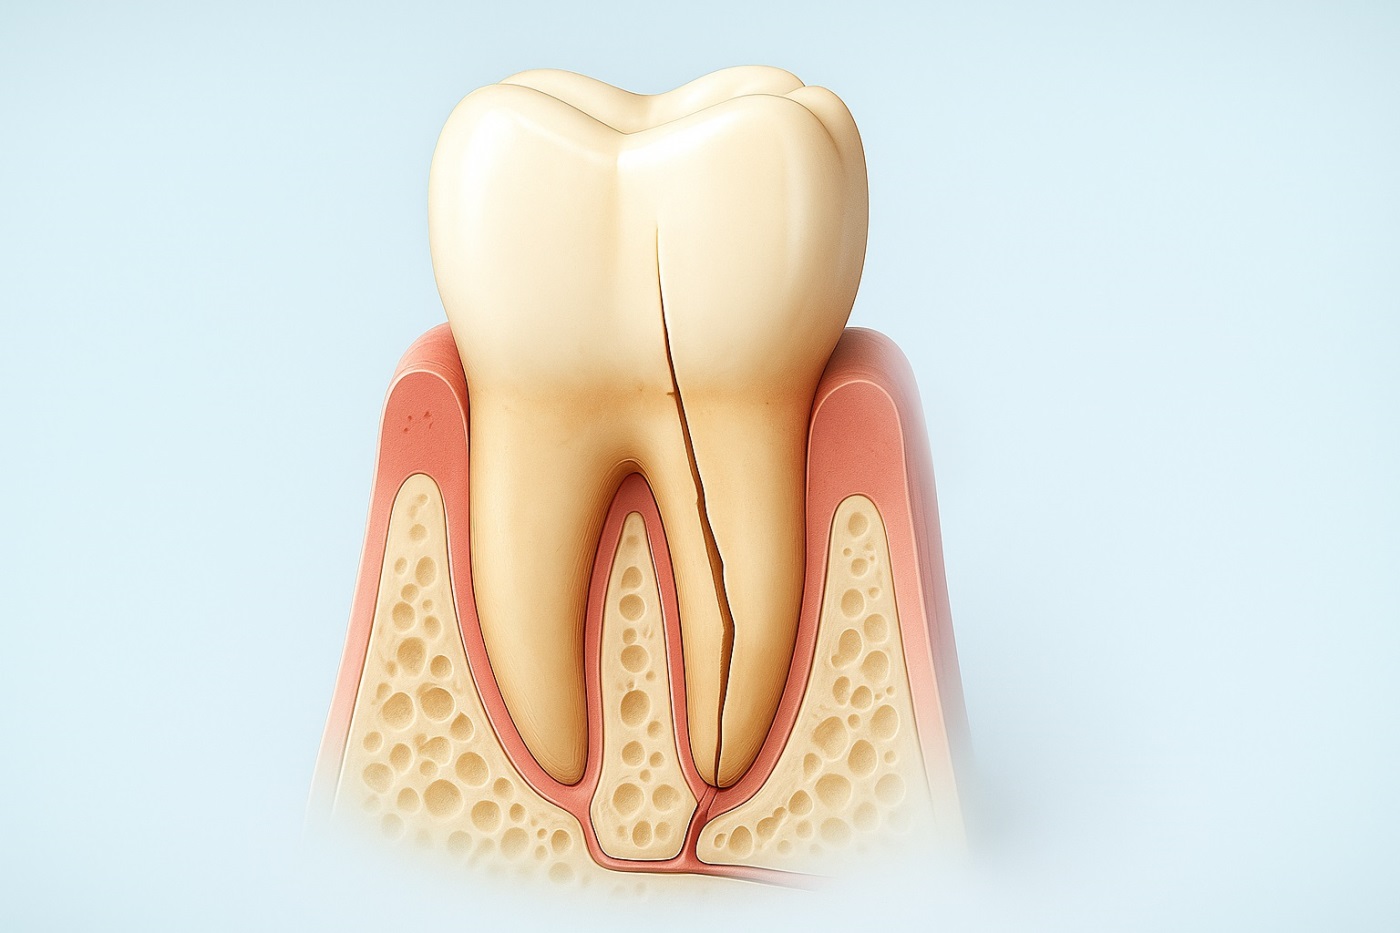

- Продольный перелом корня. Трещина, идущая вдоль корня зуба, открывает прямой путь для проникновения инфекции вглубь кости. Такие зубы, к сожалению, спасти нельзя.

- Корни зуба сильно искривлены, переплетены между собой или сращены с костной тканью.

- На верхушке корня большая киста или гранулема, которую нужно удалить вместе с зубом.